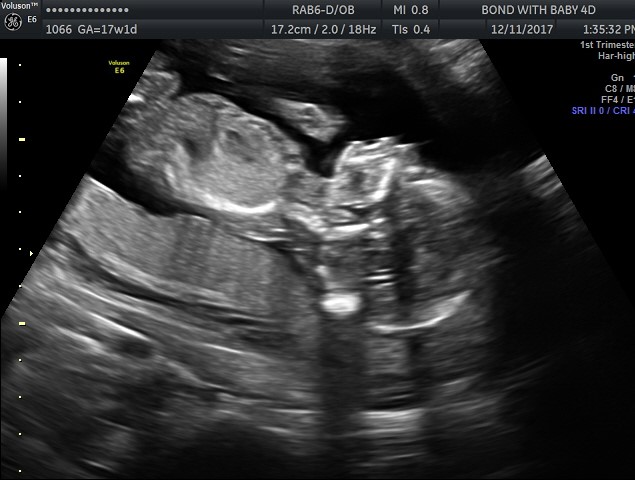

I was told a boy by this ultrasound photo, but i am having a hard time understanding the picture. Can someone help? I was sure I was having a girl, too, and this isn’t helping my confusion! https://uploads.tapatalk-cdn.com/201...d73731cca5.jpg